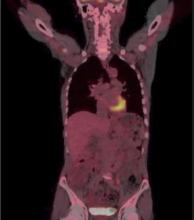

A 54-year-old male consulted for a cough. The computed tomography scan revealed a 3.8 cm mass in the left lower lobe. A bronchoscopy showed a mass in segment 6 of the left bronchus, and a biopsy revealed squamous cell carcinoma. A positron emission tomography scan showed high uptake in the left-lower lobe mass with no lymph node involvement. A single 3 cm incision was used for a VATS left-lower lobectomy and lymph node dissection for non-small cell carcinoma.